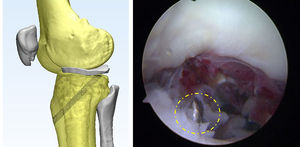

En caso de lesión de la raíz posterior del menisco lateral, se realiza de forma adicional un portal ínfero-lateral, que se posiciona a través del portal antero-medial guiado con aguja, un centímetro por encima del cuerno anterior del menisco lateral se inserta una cánula para artroscopia de hombro, este dispositivo es indispensable para evitar que se enreden las hebras con el tejido sinovial. (figura 2)

Posteriormente se identifica la lesión y se realiza su clasificación, esto con el fin de definir donde deben ponerse los implantes, se prepara el lecho de la raíz meniscal con una fresa artroscópica, se retira el cartílago y se deja una base ósea cruenta que permita la cicatrización del menisco al hueso.

Después de esto, se usa la guía tibial del ligamento cruzado en la base de la raíz, a través de este se pone un pin, y si se encuentra en la posición deseada, queda en la inserción de la raíz. Generalmente la angulación es en 60 grados, así en caso de necesitar una reconstrucción del LCA los túneles no se cruzarán.

Se realiza luego una perforación con una broca de botón para la reconstrucción del LCA, esta generalmente es de un diámetro de 4.5 milímetros. (figura 3)